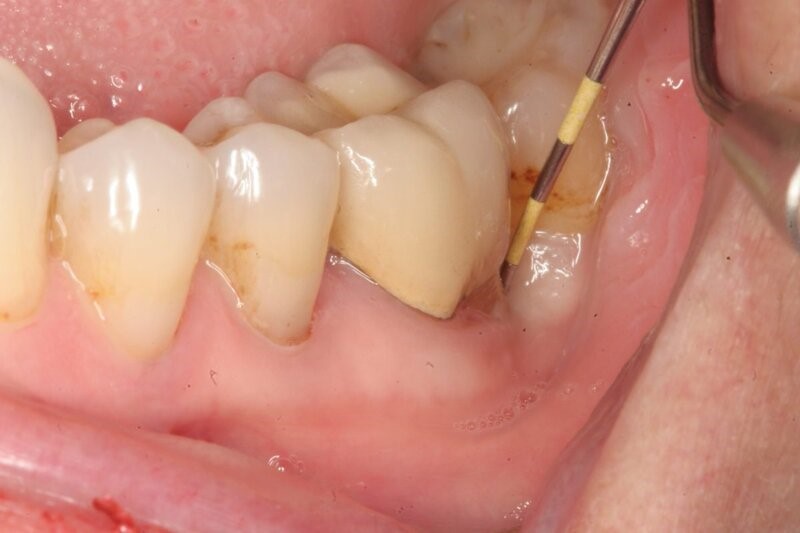

Bác sĩ sẽ kiểm tra tình trạng răng – nướu và chụp phim để đánh giá độ sâu túi nha chu, mức độ tiêu xương và lên kế hoạch điều trị phù hợp.

Trước khi bắt đầu, vùng điều trị sẽ được làm sạch và gây tê cục bộ để bệnh nhân không cảm thấy đau trong suốt quá trình.

Bác sĩ dùng dụng cụ chuyên dụng để loại bỏ mảng bám, vôi răng, vi khuẩn và mô viêm bên trong túi nha chu. Trong một số trường hợp nặng, có thể cần bóc tách nướu để làm sạch sâu hơn.

Sau khi nạo, vùng túi nha chu sẽ được làm sạch bằng dung dịch kháng khuẩn giúp ngăn ngừa nhiễm trùng và hỗ trợ mô lành nhanh hơn. Nếu có bóc tách nướu, bác sĩ sẽ khâu lại bằng chỉ nha khoa chuyên dụng để nướu phục hồi đúng vị trí.